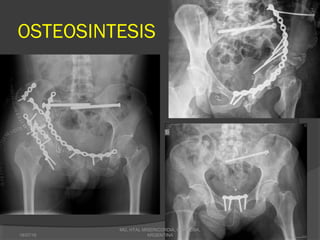

OSTEOSINTESIS

SINFISIS PUBICA

ESTA INDICADA LA RAFI CUANDO SE

FIJACION ABIERTA CON

FIJACION PERCUTANEA CON

•INDICACION, EN

•TORNILLO DE ROSCA